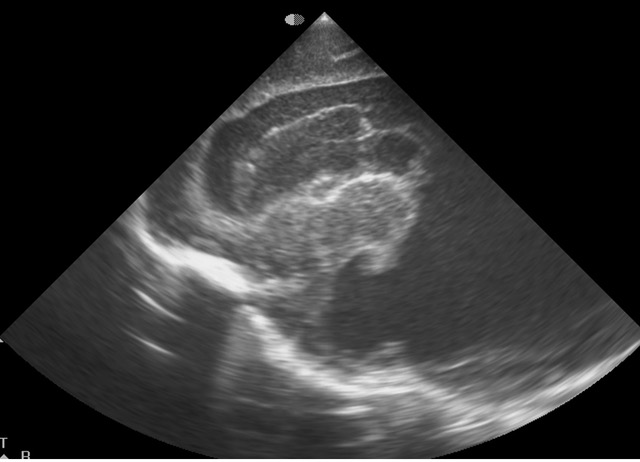

Cranial Ultrasound imaging of preterm neonate reported as a case of Intraventricular haemorrhage. CUS grading of GMH/IVH; arrowheads point to GMH, arrows to the presence of clot in the ventricle cavity; asterisk is choroid plexus.. |

Intraventricular haemorrhage in a preterm infant (Greece)

Clinical Area: Neurology

A 43-year-old primipara presented with severe hypertensive disorder of pregnancy and fetal growth restriction (FGR) at 19 gestational weeks. At 23 6/7 gestational weeks, an emergency cesarean section was conducted due to worsened hypertensive disorders of pregnancy (HDP) and a non-reassuring fetal s ...